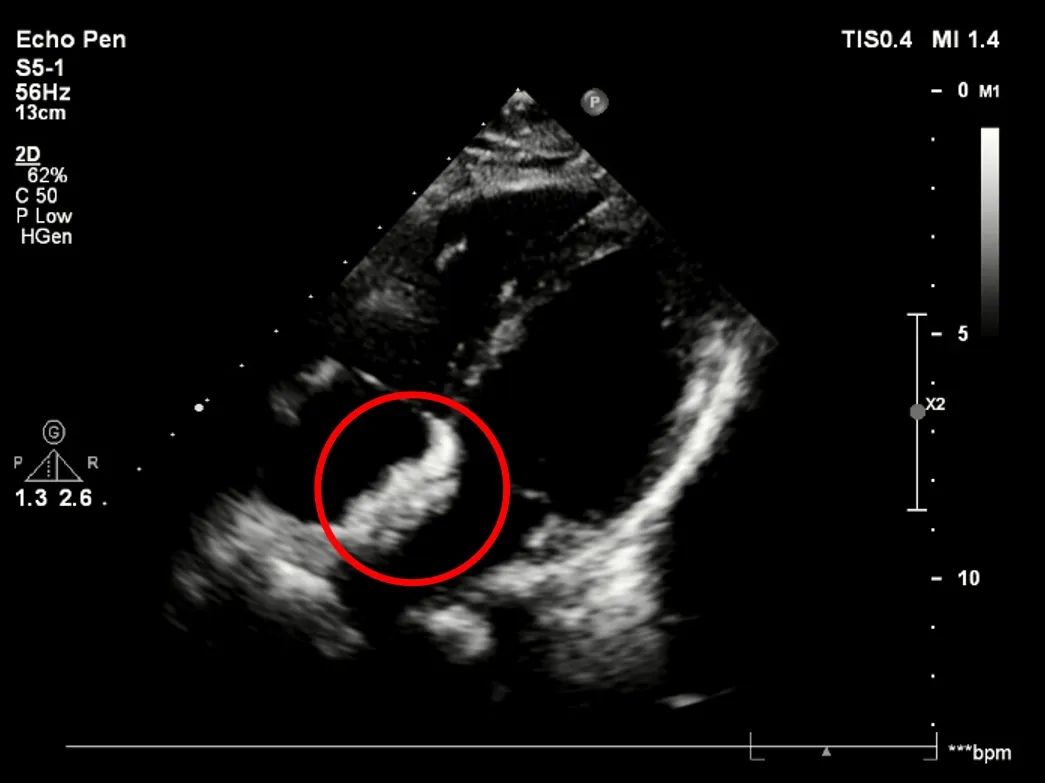

释放前超声

释放前超声下封堵器型态良好,骑跨室间隔两侧

释放封堵器

释放后超声